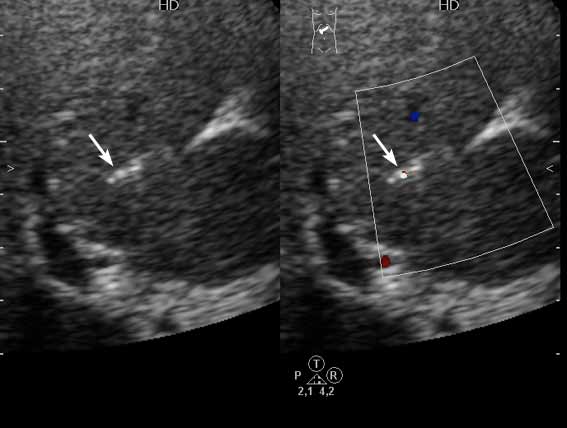

Получил данные за то, что, видимо, это мелкие конкременты в протоковой системе.

1) Эхогенные структуктуры дают твинклинг-артефакт (twinkling), характерный, например, для кальцийсодержащих образований.

2) Все пациенты, у которых наблюдалась подобная картина страдали ЖКБ, у всех был удален желчный пузырь.

Привожу еще один пример.

Женщина 70 лет,15 лет назад проведена холецистэктомия. Жалобы на боли в эпигастрии.

Наиболее вероятные варианты: хронический холангит, мелкие конкременты внутрипеченочных желчных протоков, холестероз.

на некоторый картинках - действительно - мелкие конкременты желчных ходов,

на других - просто перифокальные изменения стенок сосудов.